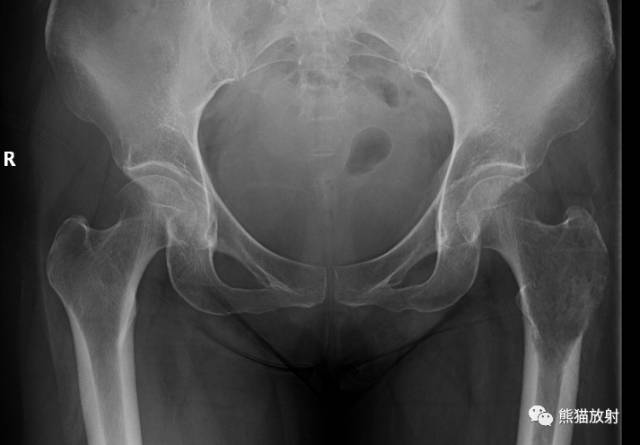

↓ 肱骨近端骨巨细胞瘤

IC型 ↓ 股骨转移瘤(肺癌)